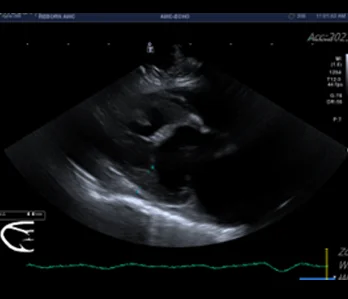

• 초음파

영상의학과는 X-ray, 초음파, CT, MRI 등 다양한 첨단 장비를 활용하여 동물의 내부 상태를 영상으로 표현하고, 이를 기반으로 정확한 진단과 치료 방향을 제시하는 역할을 합니다.

하지만 영상 장비만으로 모든 것이 해결되지는 않습니다. 장비의 수준과 함께, 이를 해석하고 판단하는 영상의학 전문 수의사의 경험과 실력이 무엇보다 중요합니다.

• 초음파 케이스 수 : 3만건 이상

다년간 다수의 케이스를 다룬 영상진단 전공 수의사들이 직접 판독 및 진단하며, 정확한 진단은 곧 효과적인 치료로 이어집니다.